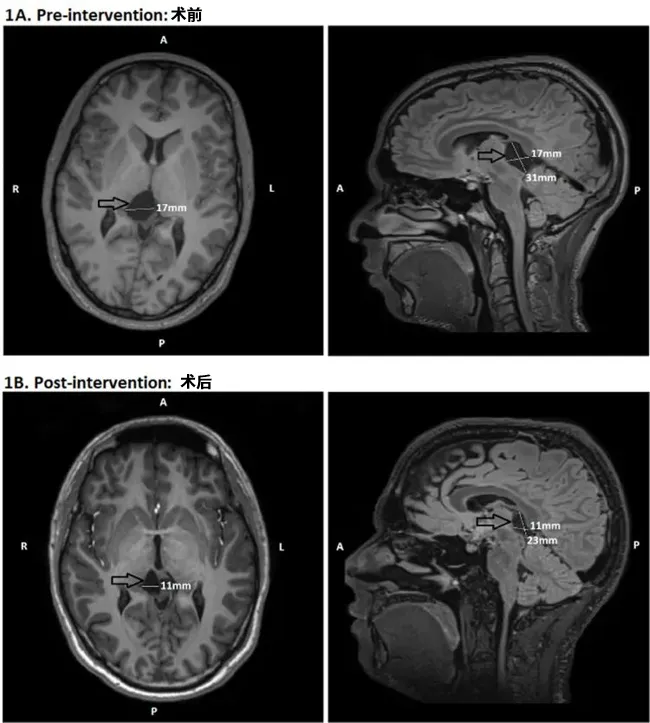

颅脑MRI给出了一个出乎所有人意料的答案:一个蛛网膜囊肿,正静静地压迫着他的丘脑和顶盖区域——那是大脑负责调节警觉与注意力的关键枢纽(图2A)。长达十年的嗜睡,根源可能在此。

改变是惊人的。术后半年复查,MRI显示囊肿已显着缩小(图2B)。更重要的是,米卡感觉自己“像是换了一个人”。白天的困倦感基本消失,注意力变得容易集中,Epworth评分从13分降至正常的6分。客观的睡眠潜伏期测试也证实,他维持清醒的能力大幅提升。

图2颅内蛛网膜囊肿手术前后MRI对比(扫描间隔12个月)。(A)术前轴位与矢状位图像:箭头指示位于丘脑及顶盖区的蛛网膜囊肿,可见明显占位效应;(B)术后6个月轴位与矢状位图像:箭头显示囊肿经开窗减压术后体积显着缩小。